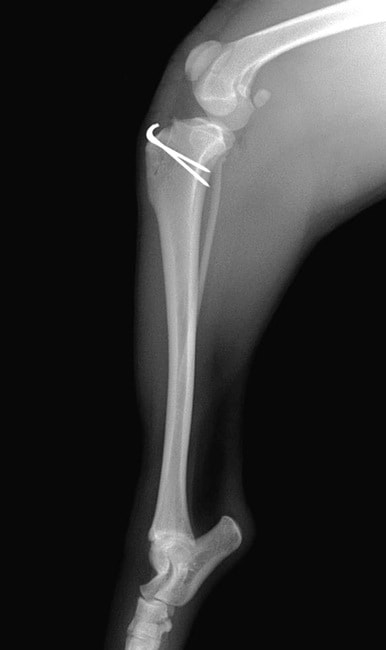

■ 症例20 ポメラニアン 8ヶ月 1.8kg

左右膝蓋骨脱臼 グレードⅢ

2ヶ月前から間欠的跛行が認められ、両膝の膝蓋骨脱臼整復術を行った。

手技は縫工筋及び内側広筋の解放、脛骨粗面の外側転位、滑車ブロック形造溝術、内外側関節包の縫縮を選択し実施した。

右側の膝蓋骨脱臼は上記手技で整復されたものの、左側はそれのみでは膝蓋骨が浮く様子が認められた。その為、PDS縫合糸にて膝蓋靱帯を1糸のみ縫合し、靱帯の縫縮を行った。

膝蓋骨脱臼は膝関節における膝蓋骨の内外側の脱臼と定義されるが、時として単純な内外の脱臼ではなく、膝蓋骨が大きく前方に浮き上がるように脱臼する場合がある。特にトイプードルやポメラニアンといった犬種に多く認められる。

内側脱臼に加えて前方への浮き上がりを矯正する為に、従来より脛骨粗面転移により膝蓋靭帯を外方と下方に引っ張り、固定する方法を選択する。膝蓋骨の前方への浮き上がりが軽度の場合は、従来法ではなく関節包の縫縮で対応していた。しかし、一部の症例で膝蓋骨の動きが悪くなり伸展機構が円滑に機能せずロボット様歩行になるケースがあった。

その為、膝蓋靭帯自体を縫縮する方法を採用した。この方法により、膝関節の伸展機構を妨げず膝蓋骨の軽度の浮きを矯正することが可能となった。

本症例の経過は良好である